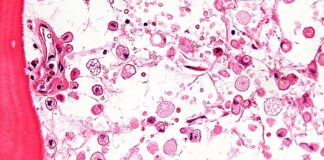

La Regione Emilia-Romagna è pronta a riattivare il gruppo di lavoro per la somministrazione delle terapie enzimatiche per le malattie lisosomiali con l'obiettivo di...